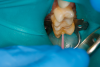

Fig 10. Occlusal approach was successful in the placement of a dual-cured bulk-fill flowable. Note the depth of box form.

Figure 10